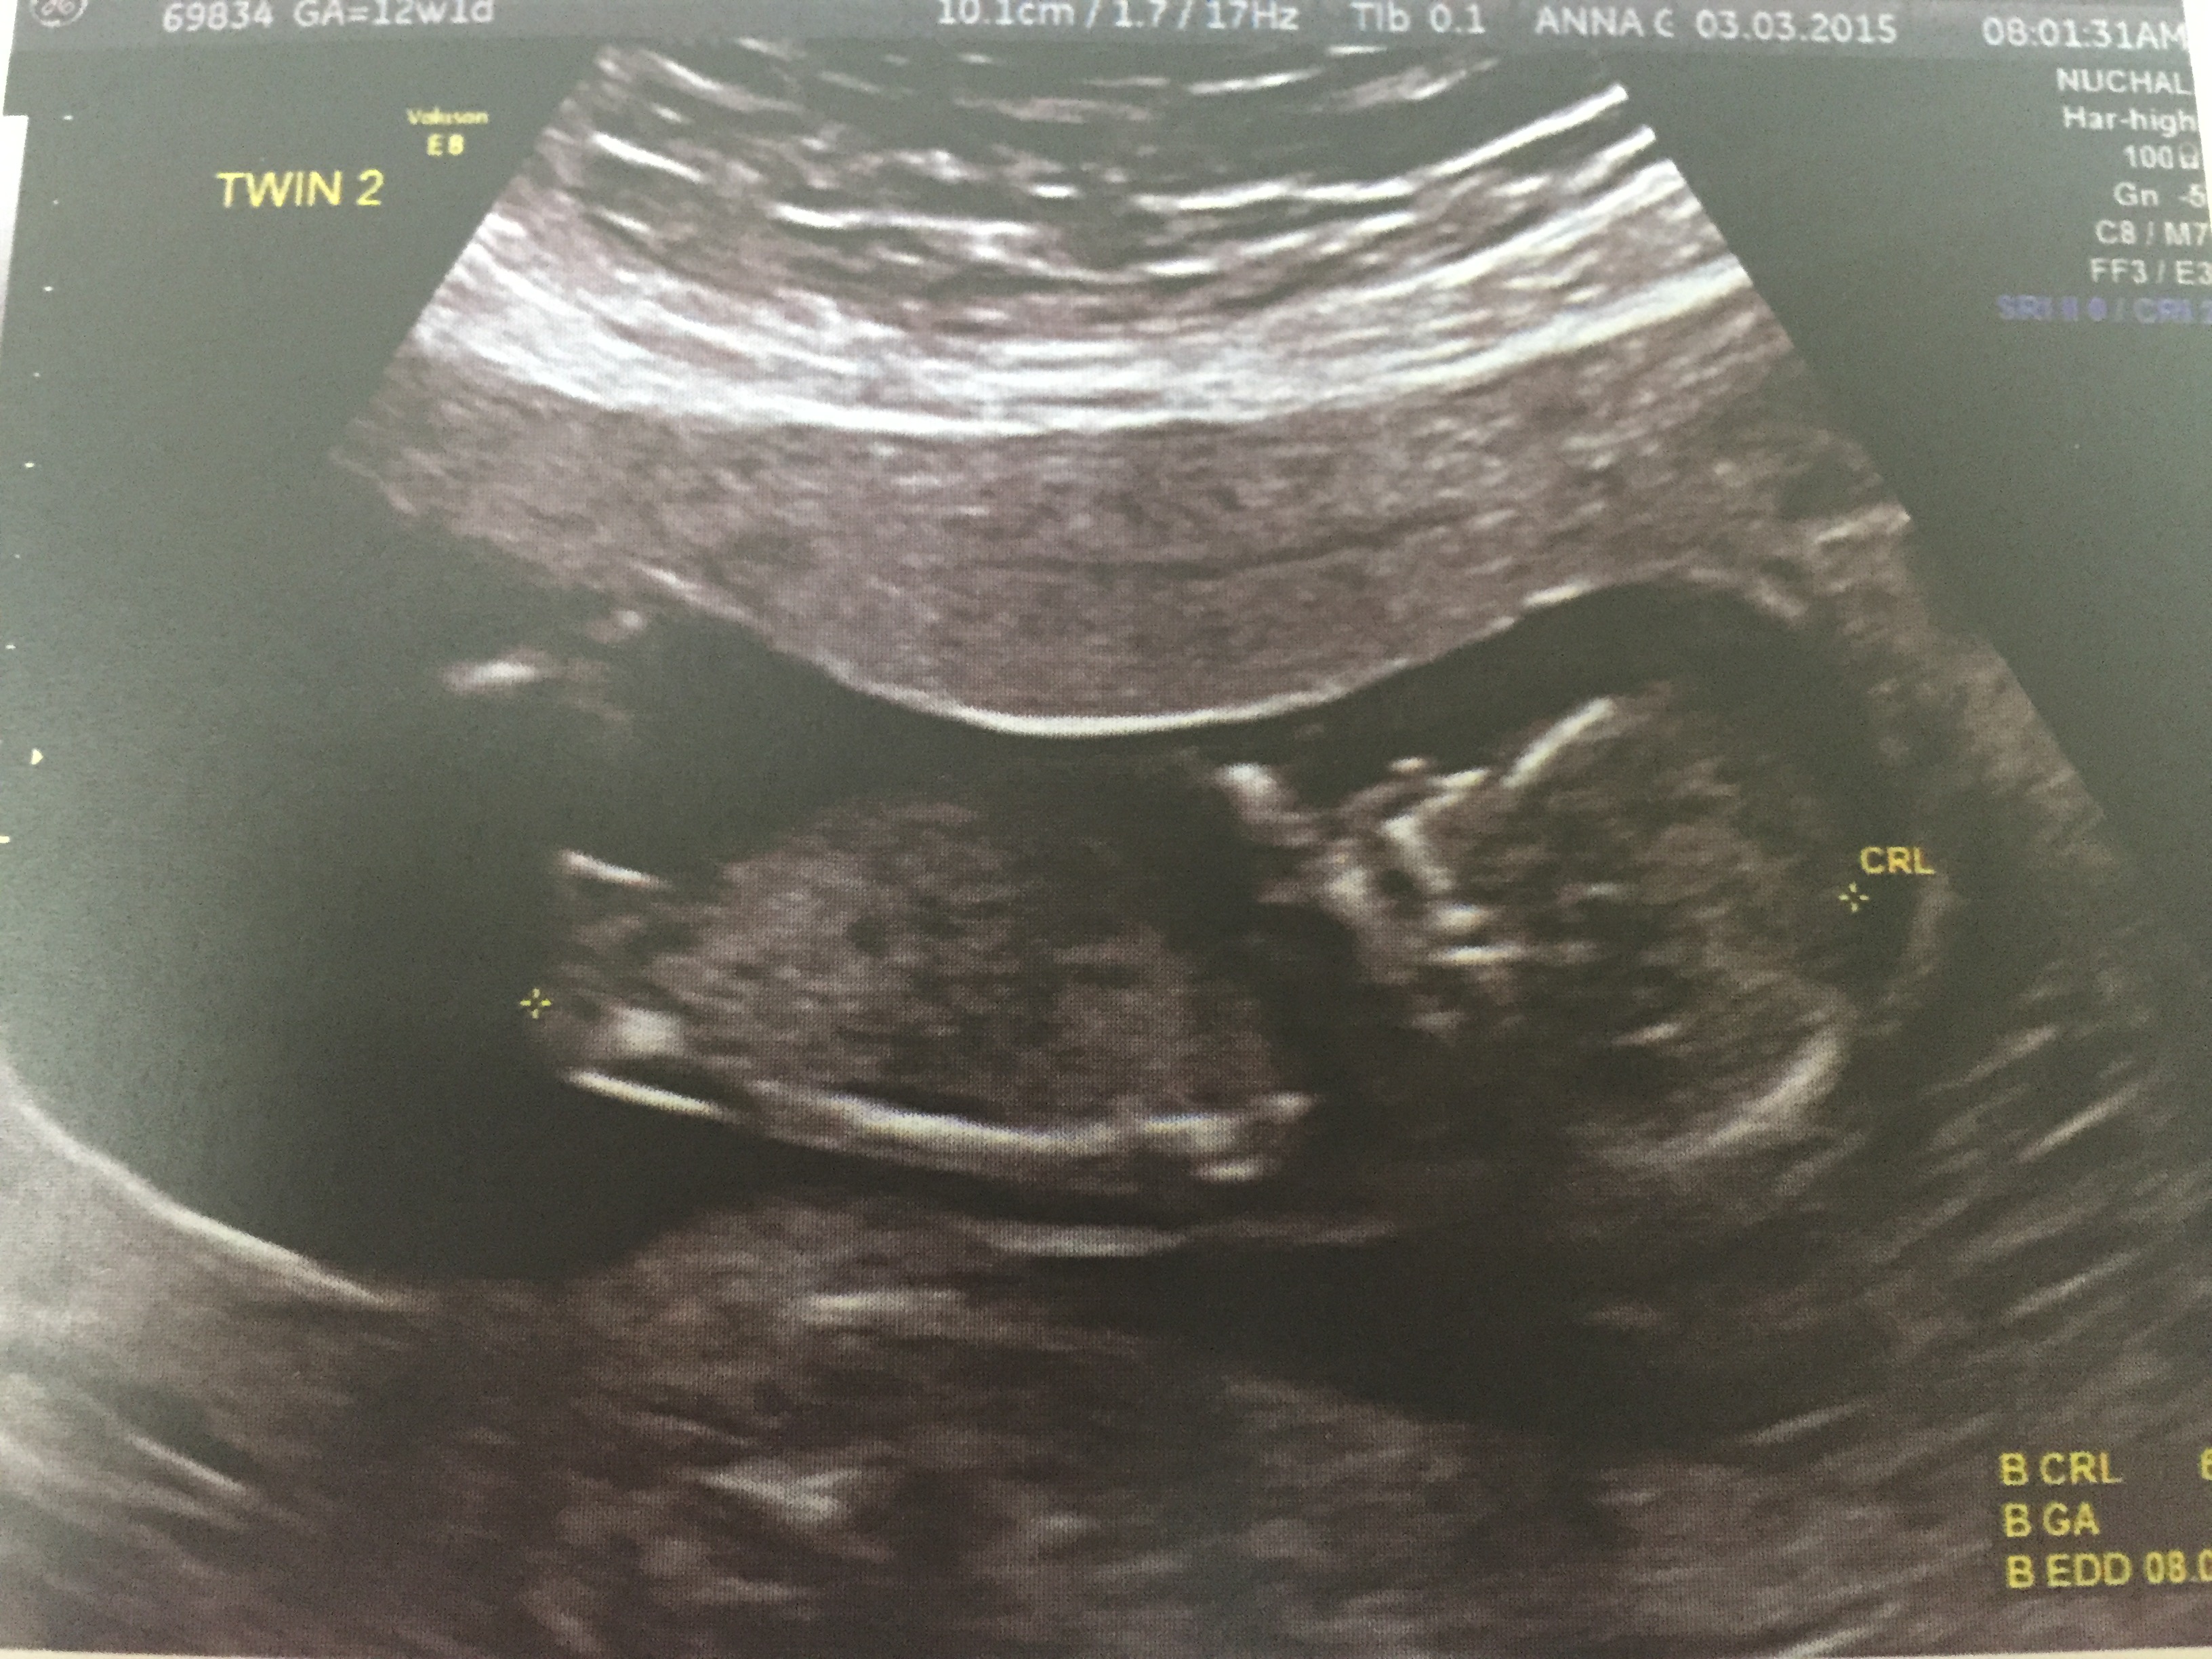

I have fraternal twins - this scan was 12 weeks 4 days, any guesses are appreciated.

Twin 1

Twin a a boy and twin b looks girly but maybe the whole nub isn't imaged. At least 1 boy

Tech said twin 1 was a boy and couldnt call twin 2!